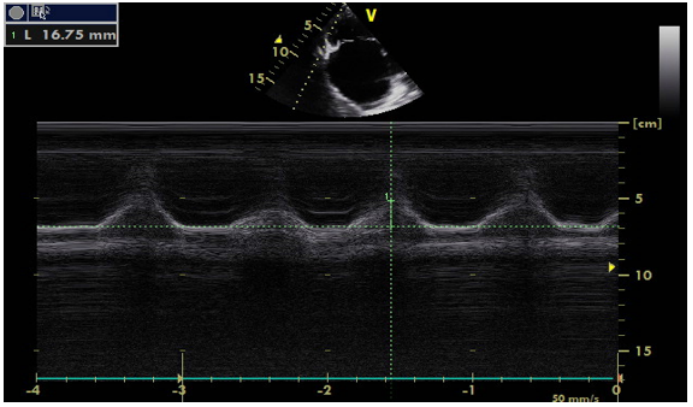

1)右房压:评估右房压时,常通过床旁超声测量下腔静脉直径及其塌陷性来估算。具体如下:需先以剑突下长轴切面为标准切面,清晰显示下腔静脉从右心房入口至肝静脉段,再借助M型超声捕捉下腔静脉随呼吸的动态变化以精准测量(图16)。测量呼气末直径(正常参考值1.5~2.5 cm,>2.5 cm提示容量过负荷),并计算塌陷率【公式:(最大直径-最小直径)/最大直径×100%】。若下腔静脉内径<1.0 cm且呼吸变化率>50%, 提示容量不足。结合下腔静脉直径与塌陷率分层判断右房压: ①当下腔静脉直径<2 cm时: 塌陷率>55%, 提示右房压为0~5 mmHg; 塌陷率30%~50%, 提示右房压为0~10 mmHg; 塌陷率<30%, 则无法估算右房压。②当下腔静脉直径>2 cm时: 塌陷率>55%, 右房压为0~10 mmHg; 塌陷率30%~50%, 右房压为10~15 mmHg; 塌陷率<30%, 右房压为10~20 mmHg。此方法利用下腔静脉呼吸变异特性, 通过超声精准测量与公式推导, 实现右房压的间接评估, 为心源性休克等场景下的容量状态、右心功能判断提供关键依据。

图片

16  M超测量下腔静脉直径